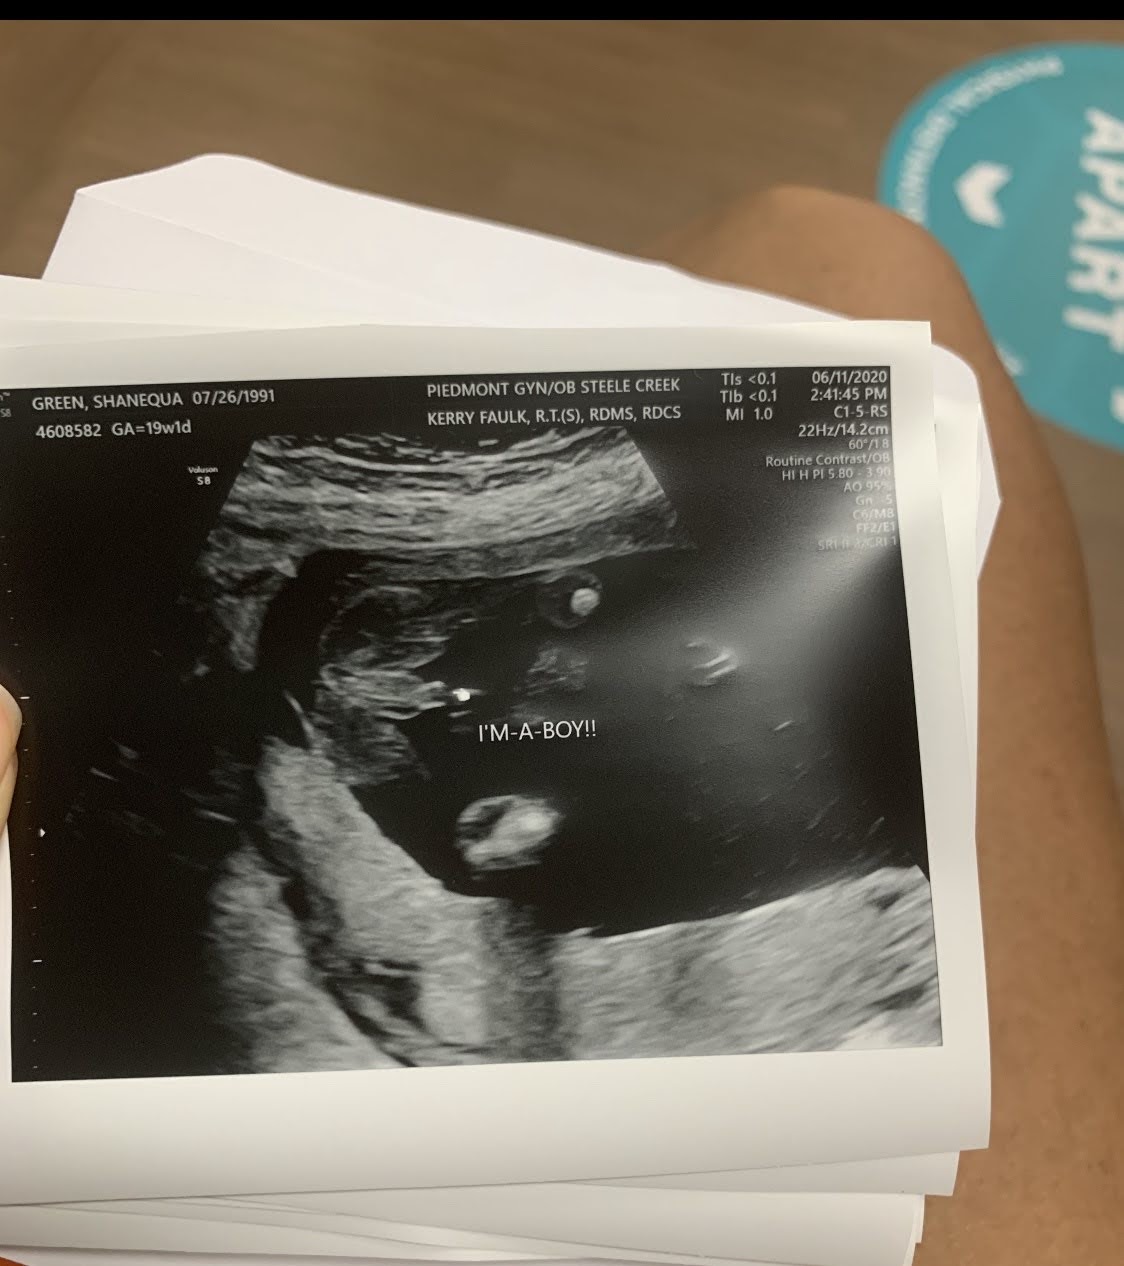

We found out the gender, ANNNNDDDD issa boy!

I am super outnumbered now lol. I was upset when I first heard the tech say it was a boy because I just KNEW that this baby was a girl! But after that initial shock the tech also told us that he is developing as he should so I am very grateful and thankful. Now I’m not gonna lie, my mind still drifts to “maybe she saw it incorrectly on the ultrasound and then on the delivery day we’ll all stare in shock at our daughter!”, but I snap out of that pretty quickly. A girl can dream.